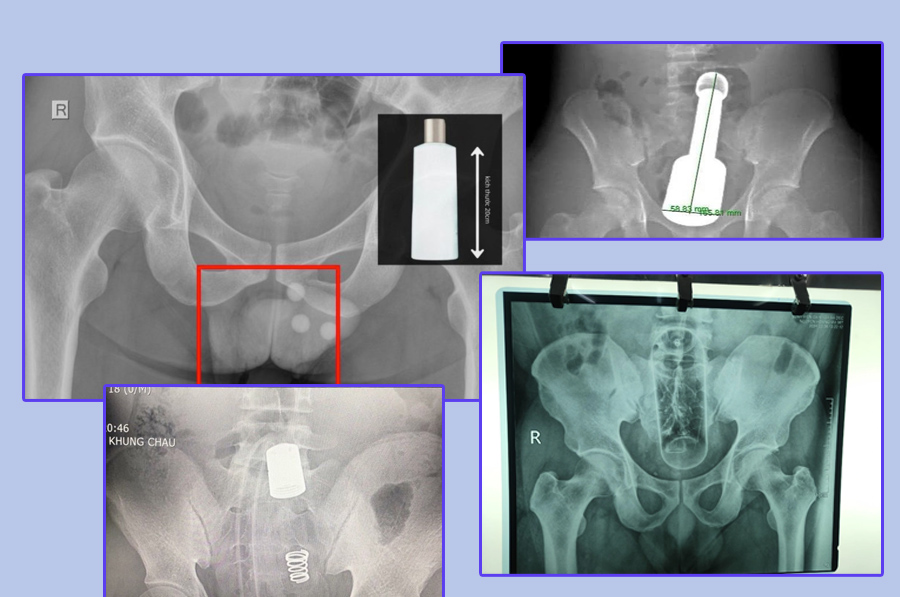

Khi bệnh nhân đến bệnh viện, bước đầu tiên là khám lâm sàng và đánh giá vị trí dị vật. Bác sĩ có thể chỉ định chụp X-quang hoặc CT để xác định kích thước, hình dạng và mức độ nguy hiểm của dị vật.

Nếu dị vật nằm thấp và chưa gây biến chứng, bác sĩ có thể tiến hành lấy ra qua đường hậu môn. Thủ thuật thường được thực hiện trong phòng thủ thuật hoặc phòng mổ, với các bước chính như: